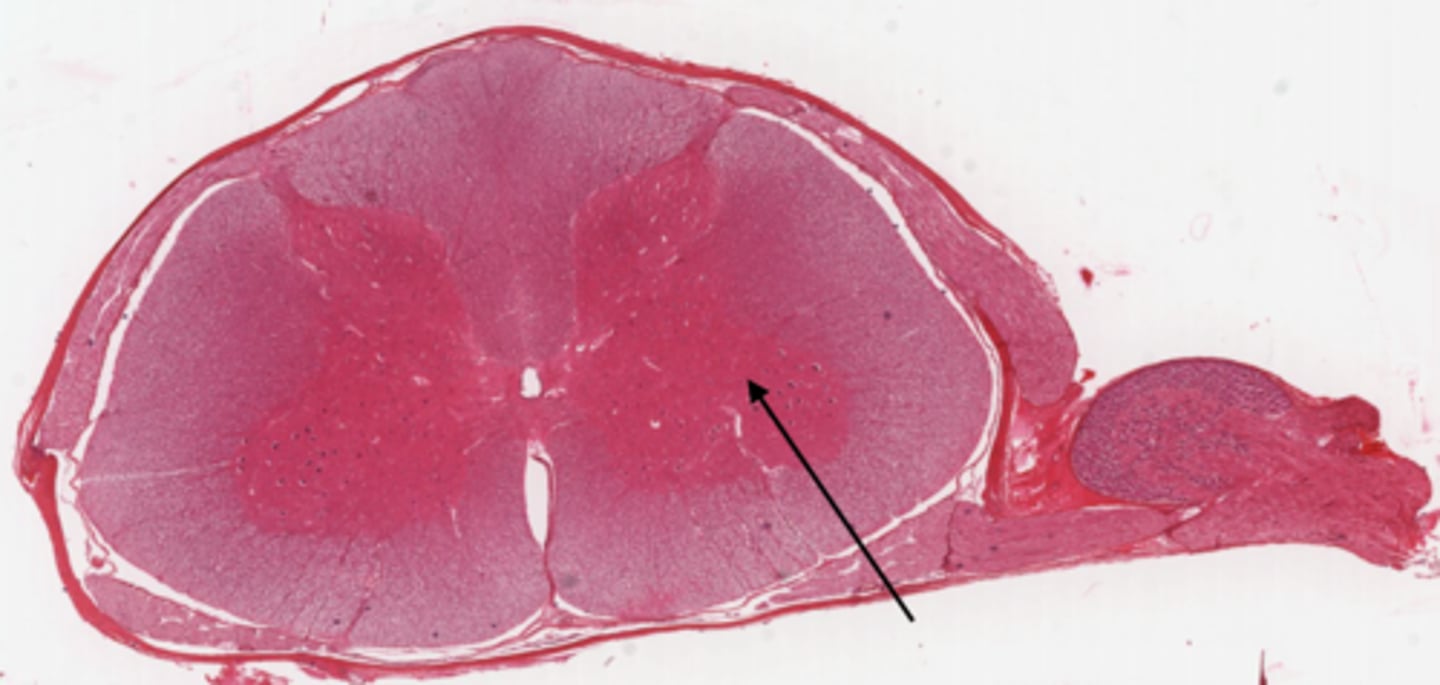

Identify the part of the spinal cord

dorsal funiculi

lateral funiculi

ventral funiculi

dorsal horn

ventral horn

dorsal root of spinal nerve

ventral root of spinal nerve

Identify the section of the spinal cord that contains nuclei

gray matter

Identify the section of the spinal cord that contains nerve tracts

white matter

central canal

Identify the part of the meninges

pia mater

arachnoid

dura mater

dorsal root ganglion